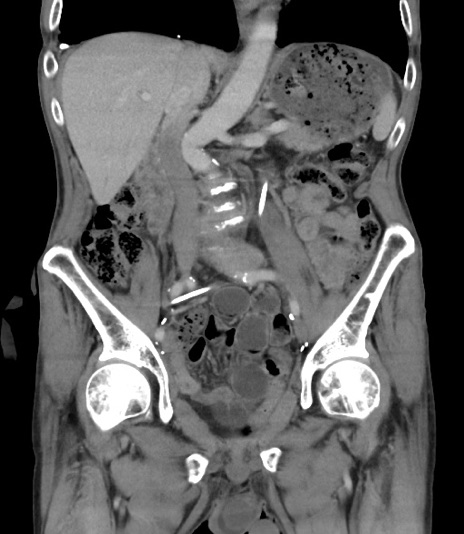

横断像

【症例】 70歳代男性

【主訴】右鼠径部腫瘤、疼痛

【現病歴】本日朝より上記主訴あり、受診。

【既往歴】膀胱癌にて膀胱全摘、両側尿管皮膚瘻

【データ】WBC 5600、CRP 0.56